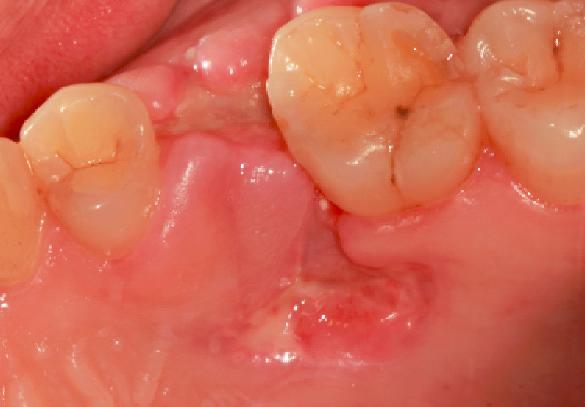

拔牙后的15分钟:血液凝块凝结

医生在拔除牙齿之后的15分钟,牙齿创口中血液会迅速聚集在伤口处凝结成血块就像平时我们身体其他地方磕碰流血的道理一样,血块凝结覆盖牙槽窝只是发自人体本能保护伤口形成保护膜,预防细菌侵袭感染。而为了促进凝血块的形成,这时,医生一般会让患者咬着棉花球30至40分钟。